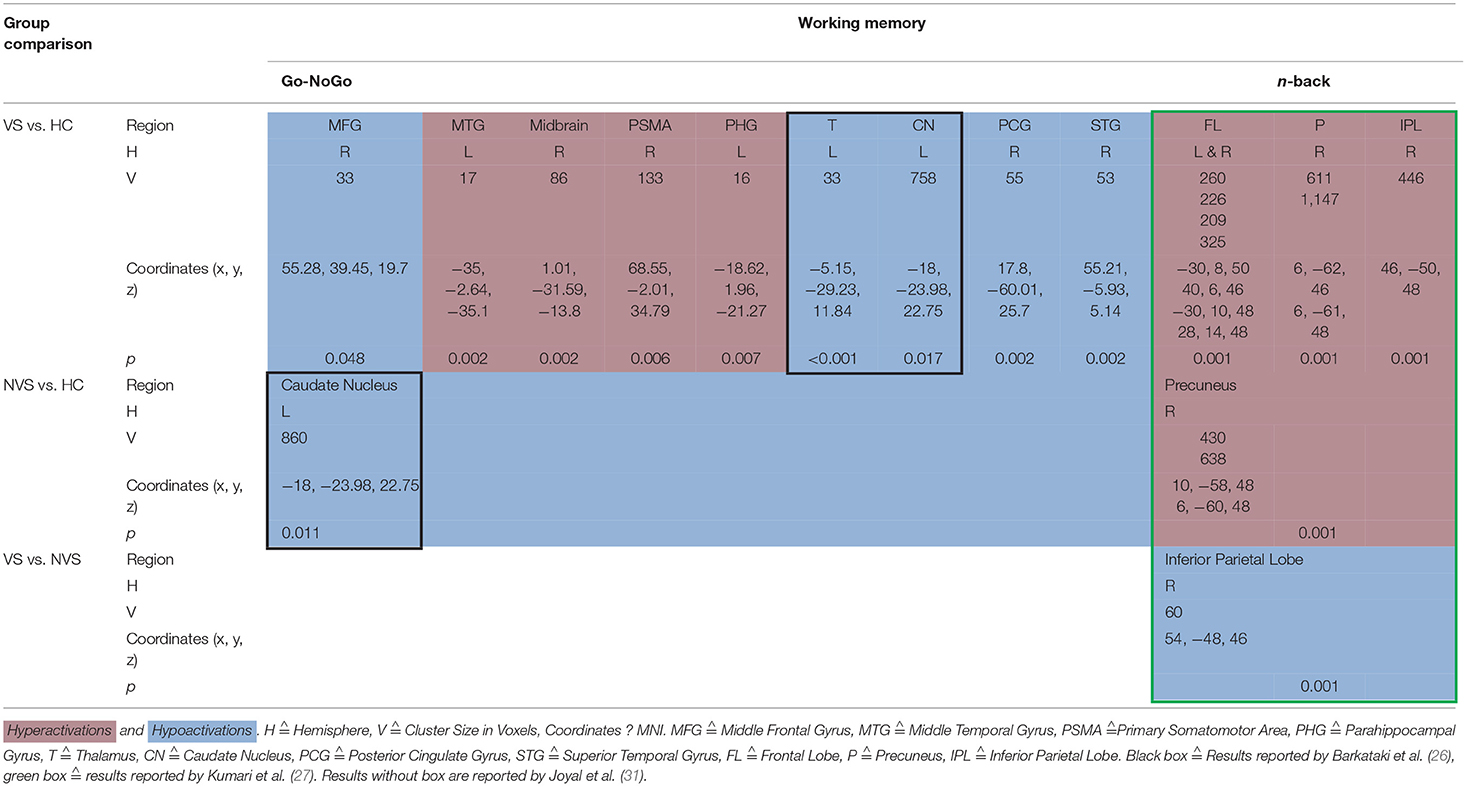

When operationalizing working memory functioning with Go/No-Go, VS vs. HC hypoactivated the right middle frontal gyrus, right posterior cingulate gyrus, and right superior temporal gyrus (31). In contrast, VS as opposed to HC hyperactivated the left middle temporal gyrus, midbrain, right primary somatomotor area, left parahippocampal gyrus (31) and hypoactivated the left thalamus and left caudate nucleus (26). NVS as opposed to HC hypoactivated solely the left caudate nucleus.

Working memory as measured by the n-back task showed that VS vs. HC hyperactivated the frontal lobe bilaterally, the right precuneus, and the right inferior parietal lobe. NVS vs. HC hyperactivated the right precuneus, while VS vs. NVS hypoactivated the right inferior parietal lobe (27). Table 3 shows an overview.

VS vs. HC hypoactivated the left thalamus and left caudate nucleus (26). The finding of decreased thalamus activation does not concord with a previous study where Manoach et al. (40) found that schizophrenia patients activated the thalamus during working memory, while HC did not.

NVS vs. HC hypoactivated the left caudate nucleus (26), a region crucial to executive functioning and working memory deficits in schizophrenia (41, 42). Caudate nucleus hypoactivation in VS vs. HC might therefore not be specific for aggression but rather for schizophrenia itself.

N-Back

Kumari et al. (27) found that VS vs. HC showed hyperactivations in the frontal lobe bilaterally, in the right precuneus and in the right inferior parietal lobe. When comparing NVS with HC, the authors observed hyperactivations in the right precuneus. These findings do not match with a previous study where patients with schizophrenia as opposed to HC showed hyperactivation of the dorsolateral prefrontal cortex, the inferior parietal cortex, and the anterior cingulate (43). Also, schizophrenia patients have been shown to hypoactivate their dorsolateral PFC and hyperactivate their ventrolateral PFC (44).

Furthermore, Kumari et al. (27) reported reduced right inferior parietal activity in the VS group compared to the NVS group and a strong negative association between right inferior parietal activity and the ratings of violence in both groups.

The frontal deficit in VS was only evident when compared to HC but not vs. NVS. These results might suggest non-significant hypoactivation in the frontal regions in NVS vs. HC. A deficit in the inferior parietal region affects executive functioning in schizophrenia and might be associated with violence (45). Furthermore, various studies show that a frontal dysfunction may be associated with violence (46).

Synthesis of Findings From Studies Using Working Memory Paradigms

In Figure 2, we provide an overview on working memory activation patterns over all reviewed studies. As shown in Figure 2A, violent as opposed to non-violent persons with schizophrenia showed hypoactivation in the right inferior parietal lobe. This is an area known for being part of the working memory network, but it has until now not been observed in specific aggression paradigms. The hypoactivation seen in this group comparison may therefore not be specific for aggression, but may represent working memory dysfunction in the VS group.

Figure 2. Working memory activations. Overview of the working memory brain activation patterns reported by the reviewed studies. Hyperactivations are shown in red, hypoactivations in blue. (A) shows the activation patterns in the group comparison VS vs. NVS with VS<NVS in blue (shown slice numbers are 210, 220, 230, 240) in the contrast 2-back vs. 0-back, (B) shows the activation patterns in the group comparison VS vs. HC with VS>HC in red (shown slice numbers are 170, 180, 190, 200) in the contrasts 1- and 2-back vs. 0-back and cognitive (go/no-go task) vs. reference condition and VS<HC in blue (shown slice numbers are 160, 170, 180, 190) in the contrast NoGo20 vs. NoGo40 and NoGo40 vs. Go and cognitive (go/no-go task) vs. reference condition, (C) shows the activation patterns in the group comparison NVS vs. HC with NVS>HC in red (shown slice numbers are 170, 180, 190, 200) in the contrast 1- and 2-back vs. 0-back.

Figure 2B shows hyperactivations of VS as compared to HC mainly in the frontal lobe and in the middle temporal gyrus. In addition, we see hypoactivations of VS as opposed to HC in the right middle frontal gyrus, the cingulate gyrus, and in the superior temporal gyrus. As frontal regions are typically involved in working memory tasks, this finding is in line with the literature.

In Figure 2C, we present the activation patterns of NVS as compared to HC. NVS hyperactivate the left caudate nucleus and precuneus. The precuneus is known to be involved in working memory processes, while the caudate nucleus usually is not. Still, the latter—as a feedback processor—might be under higher workload conditions while solving these tasks in persons with schizophrenia than in healthy controls. Also, this could be an indicator toward the hypothesis that schizophrenia patients solve working memory tasks differently, namely trying to use information from past experiences to influence their decisions in the tasks.